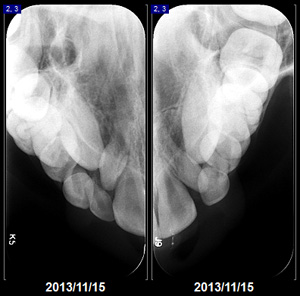

Radiografía extra oral donde vemos la articulación temporo mandibular en cuatro cortes, dos a boca abierta y dos a boca cerrada, en una sola placa.

La alteración de la articulación temporomandibular (ATM) ocurre cuando la bisagra que conecta el maxilar superior y la mandíbula inferior no trabaja correctamente. Esta bisagra es una de las articulaciones más complejas del cuerpo, es responsable de abrir y mover la mandíbula inferior hacia delante, atrás y de lado a lado. Todos los problemas que impiden el trabajo normal de este sistema complejo de músculos, ligamentos, discos y huesos, se agrupan bajo la denominación de alteración de ATM. Con frecuencia, la alteración de ATM se siente como si la mandíbula saltara o tronara o se atorara por unos segundos.